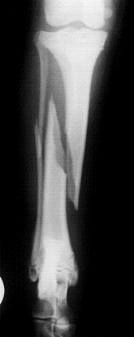

Fallbeispiel:

Unterschenkelfraktur bei einem 6 Monate alten Hundewelpen, Röntgenbild links vor und rechts nach der OP, das Implantat konnte bereits nach 8 Wochen wieder entfernt werden